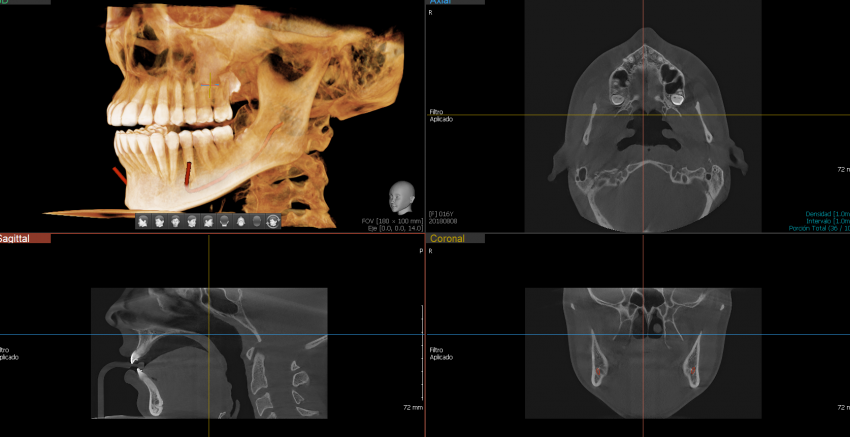

Green 16/18 ofrece una gama de campos de visión seleccionables. Multi FOV permite al usuario seleccionar el modo FOV óptimo y minimizar la exposición a áreas que no son la región de interés. Seleccione el tamaño adecuado de FOV entre 16×9/18×10, 12×9/13×10, 8×9 y 5×5 basado en una particular necesidad de diagnóstico. Cubre la región del arco completo, seno y la ATM izquierda / derecha y es adecuado para la mayoría de los casos de cirugía oral así como la cirugía de implantes múltiples. También puede medir el volumen de la vía aérea.